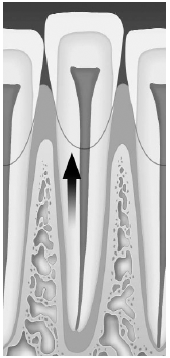

Diseases of the pulp can be secondary to trauma or operations, but clearly the most common cause is secondary to bacterial invasion after the carious destruction of the enamel. As enamel is destroyed, caries development progresses rapidly through the dentin and into the pulp chamber, causing an inflammatory reaction termed pulpitis. If the erosion caused by the bacteria is large enough to drain the developing inflammation, the patient may remain asymptomatic for a long period of time. When the drainage becomes blocked, the process progresses to the pulp and the periapical space, causing exquisite tenderness. A periapical abscess will follow the path of least resistance, which may be through the alveolar bone and gingiva and into the mouth or into the deep structures of the neck. (See Figure 11.) If the infection has progressed apically through the alveolar bone and there is localized swelling and tenderness at the base of the tooth, incision and drainage is indicated. These abscesses usually are seen at the gingival margin. Incision and drainage is performed easily by making a stab incision with a #11 blade over the area of maximal fluctuance. Small abscesses do not require a drain to be placed; however, large abscesses may benefit from a drain. A fenestrated drain or a piece of 1/4" gauze is acceptable and should be tacked to the mucosa with silk suture to prevent aspiration. Antibiotics that cover oral flora are prescribed.

| Figure 11. Deep Space Infections |